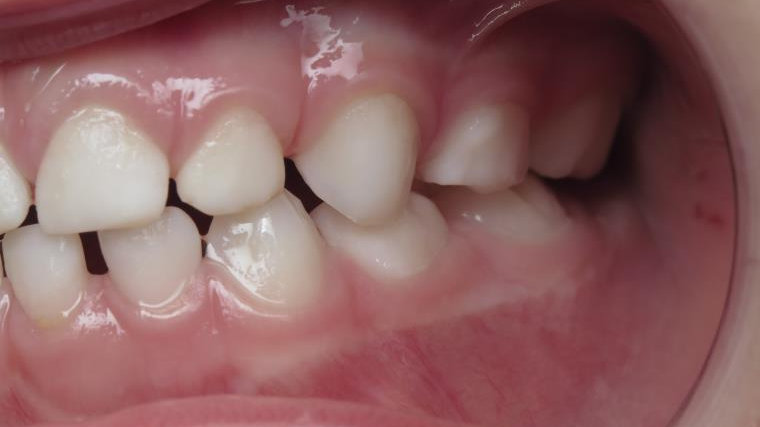

inversion des dents postérieur coté droit

appareillage mobile pendant 13 mois